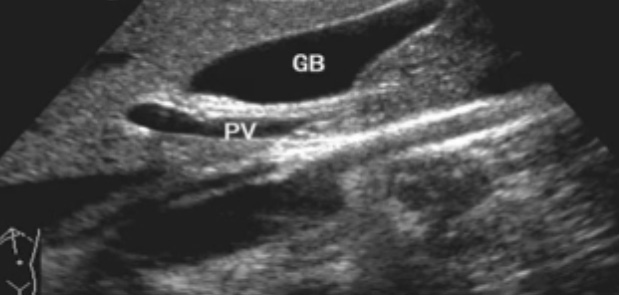

一、正常膽囊超聲圖像有的時候經(jīng)常發(fā)現(xiàn)檢查不到膽囊,其實有幾種可能性,檢查人員的技術(shù)不過關(guān)沒發(fā)現(xiàn)膽囊,就要找上級醫(yī)生會診,如果還是沒找到的話就不是技術(shù)問題。結(jié)石或腫瘤充滿膽囊,使其液腔消失,慢性膽囊炎使得膽囊萎縮或膽囊壁肥厚而囊腔消失患者已進食,膽囊處于膽汁排空的狀態(tài),膽囊先天性過小或缺失;膽囊位置極端異常(可能很低或位于左側(cè))膽囊切除術(shù)后(注意詢問病史)。